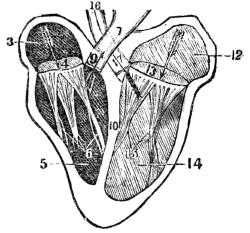

| 29. | Anatomy of the Vocal Organs, | 268 |

| 29. | Physiology of the Vocal Organs, | 272 |

| 30. | Hygiene of the Vocal Organs, | 274 |